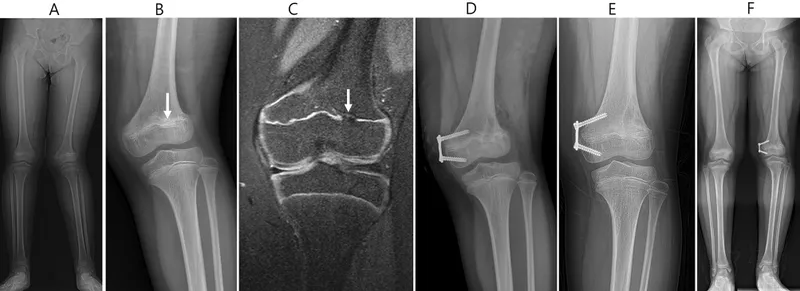

Injury Classification - Salter-Harris Shuffle

Salter-Harris classification describes fractures involving the physis (growth plate). 📌 Mnemonic: SALTER

| Type | Description (Mnemonic) | Fracture Line | Prognosis |

|---|---|---|---|

| I | Slipped / Straight Across | Through physis | Good |

| II | Above (metaphyseal fragment) | Physis & metaphysis | Good (Most common) |

| III | Lower (epiphyseal fragment) | Physis & epiphysis (Intra-articular) | Fair (Risk of arthritis) |

| IV | Through / Two (all parts) | Metaphysis, physis, epiphysis (Intra-articular) | Poor (Risk of premature fusion) |

| V | Erasure / Rammed / Ruined | Crush of physis | Worst (Growth arrest) |

- S-H III & IV: ORIF (smooth K-wires); anatomic reduction for intra-articular types. Other types may allow <2mm displacement.

⭐ Intra-articular Salter-Harris Type III and IV injuries require anatomical reduction to prevent arthritis and growth disturbance.